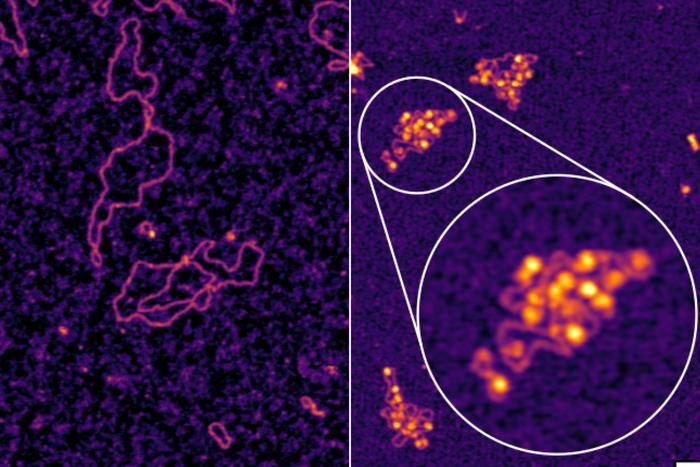

Mayo Clinic researchers have made a groundbreaking discovery in the field of ovarian cancer treatment by identifying a novel immunotherapy…